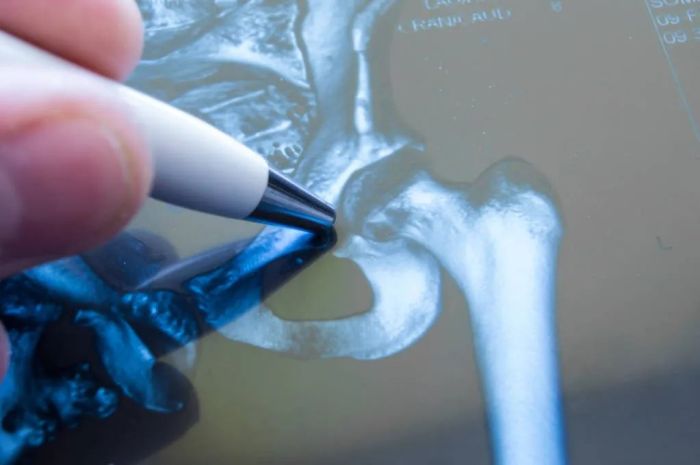

据了解,47岁的刘大姐被诊断为双髋关节骨性强直,因强直性脊柱炎导致双髋关节疼痛和活动受限已超过十年,最佳治疗选择是进行人工全髋关节置换术。

骨科一病区行政主任易平介绍,强直性脊柱炎(AS)是一种慢性进行性炎性疾病,主要侵犯脊柱,并可能累及如髋关节等骶髂关节和外周关节。如果髋关节出现疼痛、活动受限等症状,需要及时就诊。当髋关节因炎症导致关节破坏而出现纤维强直或骨性强直时,人工关节置换可能是恢复功能的必要措施。